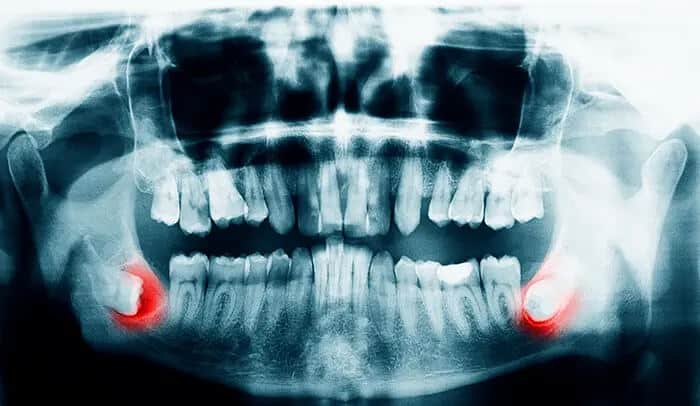

Your mouth experiences many changes within your lifetime A major dental milestone that usually occurs between the ages of 17 and 25 is the appearance of your third molars, your last adult teeth to appear: your wisdom teeth. Your wisdom teeth can be just as useful as any other tooth. if they grow in correctly, healthy wisdom teeth can help you chew. Unfortunately, that’s usually the expectation, not the rule. Sometimes when your mouth is too crowded for your wisdom teeth to grow in normally, they become impacted. A partially impacted wisdom tooth is when only part of the tooth emerges and is visible. A fully impacted wisdom tooth trapped below the surface of your gums and is not visible. When wisdom teeth erupt and have no room to grow or are impacted they can damage neighboring teeth. Poorly positioned, impacted or partially impacted wisdom teeth can make it difficult to floss, making teeth prone to tooth decay and can cause food to get trapped causing bacteria to enter your gums, causing chronic gum infection and bad breath. Not all impacted wisdom teeth are symptomatic. You may not experience any symptoms from impacted wisdom teeth. In fact, you can be free of painful symptoms for many years; however, that does not mean that your gums and teeth in surrounding areas are “infection free”. We help you maintain strong, healthy teeth, including your wisdom teeth. We monitor and evaluate your wisdom teeth, in addition to your overall dental health. We look for symptoms of impacted or erupted wisdom teeth and, together, we will discuss the right course of treatment in order to maintain your healthy smile. If you are experiencing pain, facial swelling or red, swollen or bleeding gums in the areas behind your last molars BE WISE! call our office for an evaluation of your wisdom teeth.